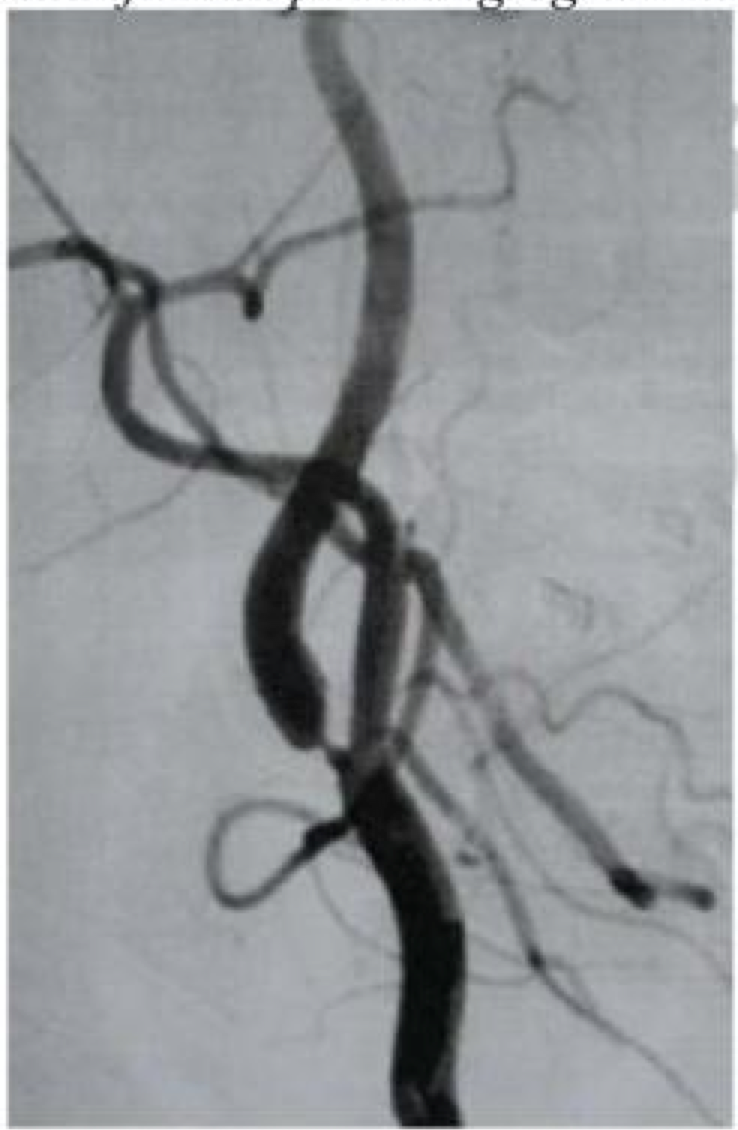

Kelainanyang dijelaskan pada angiogram karotid intern servik di bawah ini?

A. Diseksi Arterial

B. Arteritis takayasu

C. Sindroma MARFAN

D. Displasia Fibromuskular

E. Mitokondrial

D